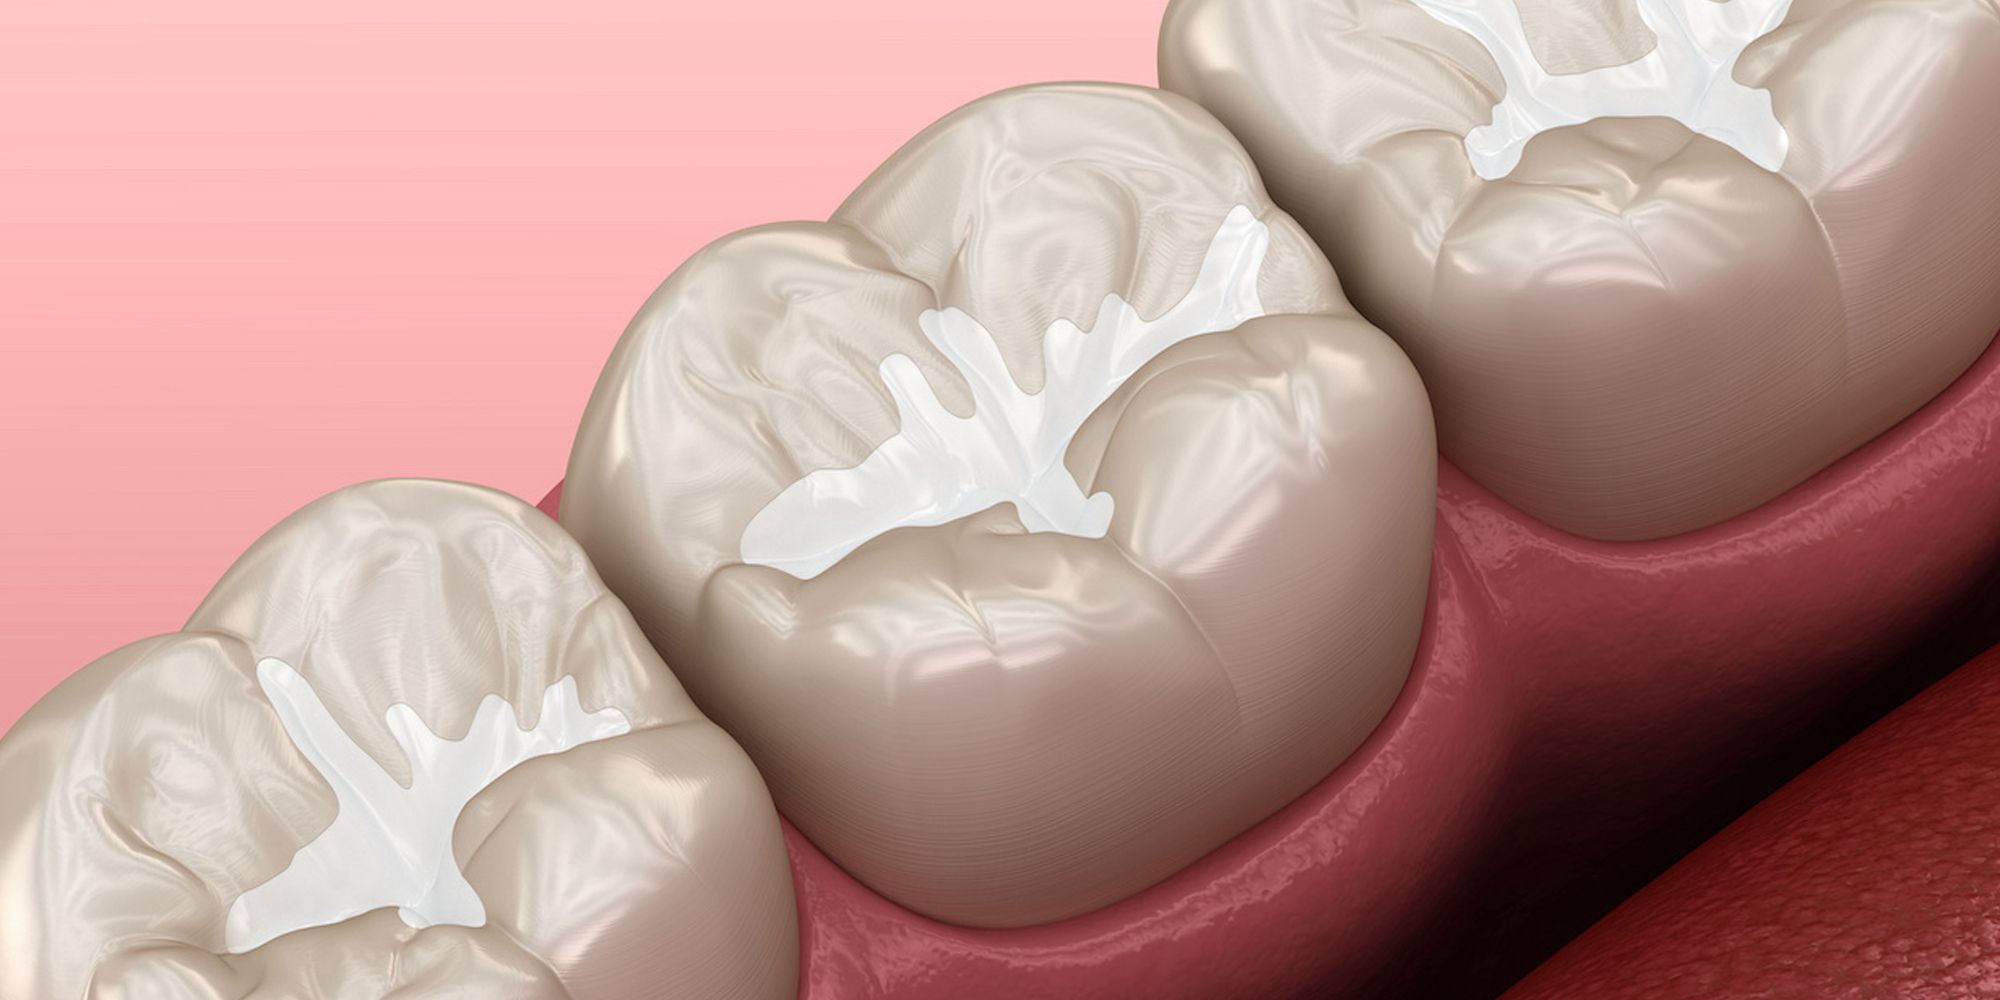

Από την άλλη τα sealants είναι λεπτές προστατευτικές επικαλύψεις που εφαρμόζονται στις μασητικές επιφάνειες των μόνιμων δοντιών. Αποτελούν μία από τις πιο αποτελεσματικές μεθόδους πρόληψης της τερηδόνας, καθώς σφραγίζουν τις βαθιές αυλακώσεις των δοντιών, εμποδίζοντας τη συσσώρευση τροφών και πλάκας.

Από τις πιο σύγχρονες θεραπείες που κυριολεκτικά θωρακίζουν τα παιδικά δόντια, είναι τα sealants μια από τις πιο αποτελεσματικές προληπτικές μεθόδους για την πρόληψη της τερηδόνας. Γνωστά και ως επικαλύψεις δοντιών, τα sealants παρέχουν μακροχρόνια προστασία, ειδικά στις μασητικές επιφάνειες, όπου η τερηδόνα εμφανίζεται πιο συχνά. Ας δούμε στη συνέχεια αναλυτικά τι είναι τα sealants, πώς εφαρμόζονται, και ποιο είναι το κόστος της διαδικασίας.

Τα sealants είναι λεπτές, διάφανες ή λευκές επαλείψεις που τοποθετούνται στις αυλακώσεις των μασητικών επιφανειών των μόνιμων δοντιών. Αυτά τα σημεία είναι ευάλωτα στη συσσώρευση τροφών και μικροβίων, κάτι που τα καθιστά ιδανικά για την ανάπτυξη τερηδόνας. Με την εφαρμογή sealants, οι αυλακώσεις σφραγίζονται, αποτρέποντας τη δημιουργία προβλημάτων.

Για να τοποθετηθούν σωστά και αποτελεσματικά τα sealants ο οδοντίατρος ακολουθεί τα εξής βήματα: